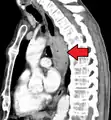

Additional testing is needed to assess how much the cancer has spread (see § Staging, below). Computed tomography (CT) of the chest, abdomen and pelvis can evaluate whether the cancer has spread to adjacent tissues or distant organs (especially liver and lymph nodes). The sensitivity of a CT scan is limited by its ability to detect masses (e.g. enlarged lymph nodes or involved organs) generally larger than 1 cm.[43][44] Positron emission tomography is also used to estimate the extent of the disease and is regarded as more precise than CT alone.[45] PET/MR as a novel modality has shown promising results in preoperative staging with fair feasibility and good correlation in comparison to PET/CT. It can enhance tissue differentiation with lowering the radiation dose to the patient.[46] Esophageal endoscopic ultrasound can provide staging information regarding the level of tumor invasion, and possible spread to regional lymph nodes.

Contrast CT scan showing an esophageal tumor (axial view)

Contrast CT scan showing an esophageal tumor (coronal view)